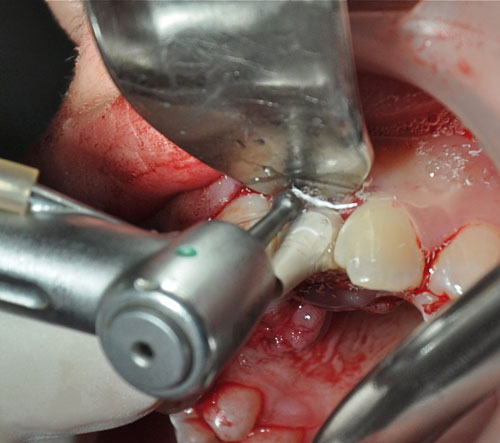

Abordamos con fresa lanceolada para el marcaje del lecho y expandimos con expansores roscados para densificar un hueso de Tipo IV

Realizamos un colgajo vestibular y palatino sin incisión de descarga para preservar lo mas posible el aporte sanguíneo

Instalación de implantes

Instalación de implantes

Instalación de implantes

Instalación de implantes